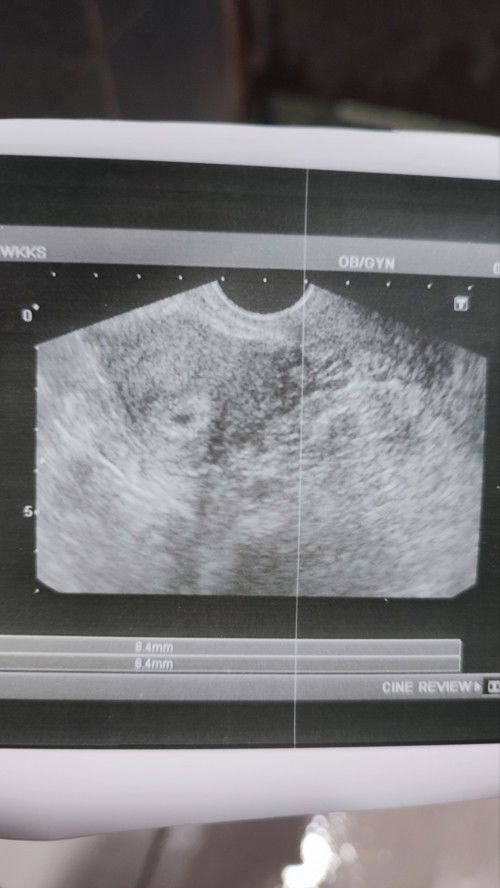

PREGNANT 7W1D

Hai, kemarin saya ada buat scan kat hospital swasta then kantung saya tak nampak but upt naik double line... then kena refer to hospital kerajaan untuk buat scan melalui vagina... after 4 hours waiting, turn saya untuk buat scan. Then alhamdulillah kantung nampak. Tapi saya tetap curious kenapa scan biasa tak nampak kantung. So saya maw tanya normal kah kandungan 7 minggu saiz janin macam ne ?. lastly, doakan saya dan kandungan saya sihat dan selamat sehingga saya melahirkan nya.. Amin #firsttime